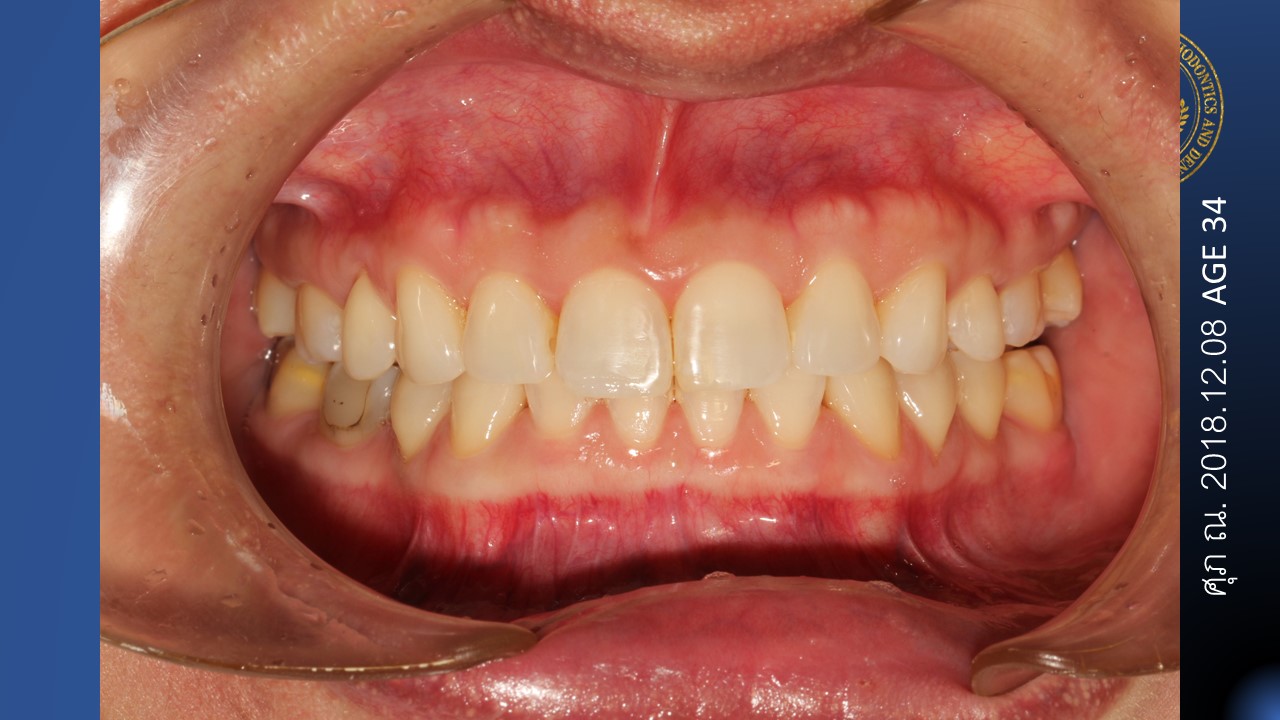

- Optimal interincisal angle was not settle up. Vertical control was not performed. The bite become deeper and deeper with time

- Finishing occlusion will be even more than worst. The operator was totally underestimate the side effects of closing 10 mm on the left side and 7 mm on the right side space in the mandible

- The result of the treatment is nice smile but the patient cannot properly chew